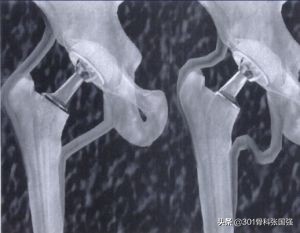

发育性髋关节发育不良合并髋关节脱位

大家也习惯叫“先髋”,当合并髋关节脱位时,患肢会出现严重的短缩,软组织也存在挛缩,如果将其下拉到应有的长度,很有可能会出现神经、肌肉、血管的牵拉损伤,部分可能还需要做短缩截骨,这也是在髋关节置换中难度系数较大的病例。

不过,这些年随着假体的改进和手术技术的提高,已经可以在绝大部分的病友中获得术后的肢体长度平衡,并且1公分以内的差异,也不会让大家感到不适。